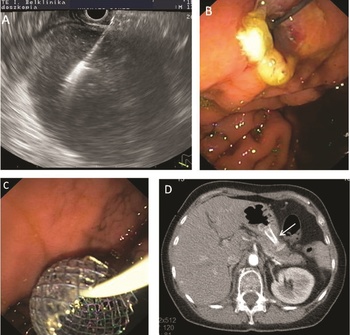

Az EUH az utóbbi évtizedben minimálisan invazív módon terápiát is képes nyújtani, és ezáltal sebészi vagy radiológiai beavatkozásokat kiváltani, mivel azoknál eredményesebb, kevesebb szövődménnyel jár vagy költséghatékonyabb (Venkatachalapathy–Nayar, 2017). Az akut hasnyálmirigy-gyulladás következtében kialakuló peripankreatikus folyadékgyülemek (pszeudociszta és walled-off necrosis) kezelésében randomizált vizsgálatok eredményei alapján az EUH-vezérelt drenázs az elsőként választandó technika, mert hatékonyabb, mint a korábban végzett sebészi vagy perkután drenázs (van Brunschot et al., 2018). AZ EUH-drenázs előnye, hogy a gyomor lumenében bedomborodást nem okozó folyadékgyülemek is jól ábrázolhatók, kiválasztható a legrövidebb szúrási útvonal, elkerülhetők a területen futó erek. A beavatkozás során vékony tűvel fisztulajáratot hozunk létre a gyomor ürege és a folyadékgyülem között, amit vezetődróton feltágítunk, majd sztentet vezetünk a drenázs fenntartása céljából a folyadékgyülembe (10. ábra). Ugyanezen technikát alkalmazva 1) epe­úti elzáródás esetén a sztent epeútba ültetésével és az epe gyomorba/nyombélbe vezetésével a sárgaságot tudjuk megszüntetni; 2) epehólyag-gyulladás esetén az epehólyagot az emésztőrendszerbe drenálva gyógyítjuk meg a gyulladást; 3) a gyomorkimenet elzáródásakor a gyomor és a vékonybél között tudunk összeköttetést létrehozni, és tudjuk biztosítani a beteg táplálását.

Jegyzet elhelyezéséhez, kérjük, lépj be.!

10. ábra. Endoszkópos ultrahangvezérelt walled-off pankreász nekrózis (WOPN) drenázs. Endoszkópos ultrahangvezérléssel, a legrövidebb és érmentes útvonalon tűvel szúrjuk meg a WOPN-t (A). Vezetődróton ballonnal a fisztulajáratot feltágítjuk (B), és egy fedett öntáguló fémsztent behelyezésével biztosítunk tartós összeköttetést a gyomor és a WOPN között (C, D)